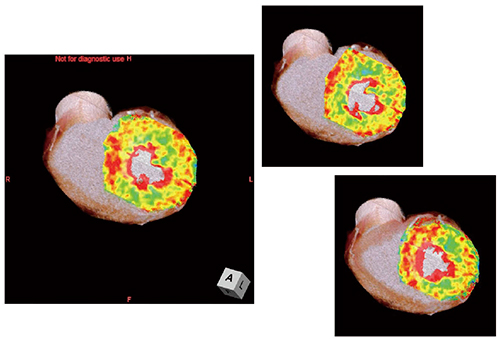

●症例1:Normal case

57歳,女性。負荷Dynamic CTPでは全体に心筋の信号が均一で非常に安定している(図1)。また,Definition Flashのコンソールに搭載されたソフトウェア“syngo Volume Perfusion”により,5分程度の解析でVoxel-wise MBF mapを作成することができる。これをCTAとフュージョンすることで冠動脈の支配域と,その血流状態が明瞭に把握可能であり,正常例では外膜側と比べると内膜側に向かってグラディエントのついた心筋血流値となっているのがわかる(図2)。遅延造影CTでも,全体に均一なCT値が得られている(図3)。

図2 症例1:Voxel-wise MBF mapと |